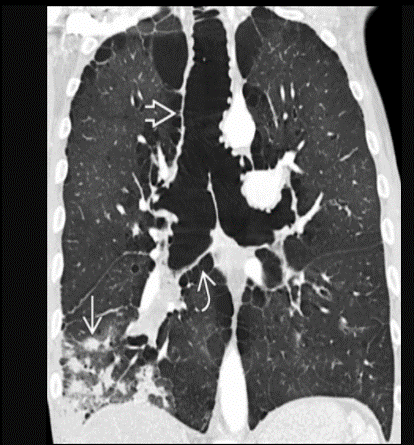

50 yo M with chronic cough and recurrent infections

Tracheobronchomegaly (Mounier-Kuhn syndrome)

Dilatation of trachea & central bronchi that impairs ability to clear mucus

Atrophy or absence of elastic fibers & thinning of smooth muscle layer in trachea & main bronchi